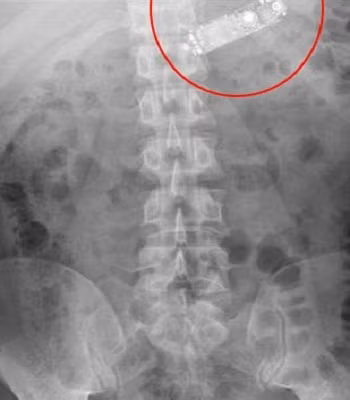

| Vị trí chiếc điện thoại trong dạ dày bệnh nhân. Ảnh:Obinna Obinwa. |

Sau khi chụp X-quang, các bác sĩ xác định vị trí chiếc điện thoại nằm trên vùng thượng vị ngay phía trên dạ dày. Nhóm điều trị quyết định chờ 18 tiếng để bệnh nhân tự đào thải chiếc điện thoại theo cách thông thường. Nhưng sau gần một ngày chờ đợi, nó vẫn ở trong dạ dày bệnh nhân và chuẩn bị đi vào ruột non để vào đường tiêu hóa, khiến các bác sĩ quyết định tiến hành phẫu thuật.